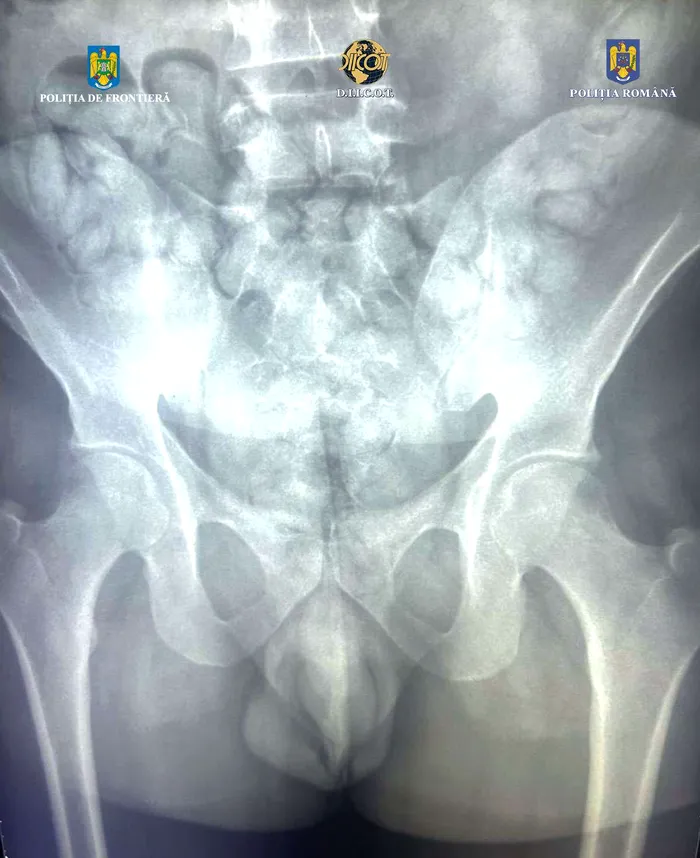

Drogurile erau fixate cu bandă adezivă pe picioare, iar o parte din ele au fost găsite în abdomenul bărbatului, în urma scanării cu raze X.

A fost dus la o unitate spitalicească, unde, pe parcursul internării, ar fi eliminat 62 de cașete, ce conțineau aproximativ 350 de grame de substanță pulverulentă, care în prezent este în curs de expertizare.

Pe picioare avea două pachete ce conțineau aproximativ 500 de grame de cocaină, porționată în 78 de cașete.